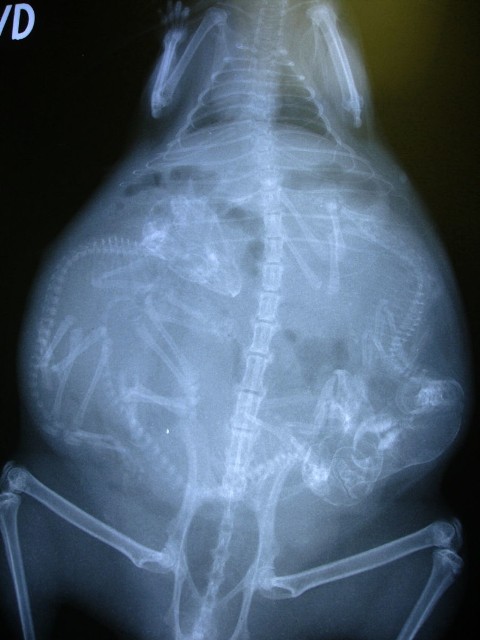

Մենք բոլորս լավ պատկերացնում ենք, թե ինչպես է անցնում մարդու հղիությունը, և շնորհիվ ժամանակակից տեխնոլոգիաների՝ կարող ենք տեսնել երեխային մայրիկի արգանդում հղիության ամենավաղ փուլում։ Իսկ ինչպե՞ս է ընթանում կենդանիների հղիությունը։ Մասնագետները, ովքեր հոգ են տանում հղի կենդանիների մասին, ներկայացրել են նրանց ռենտգենային և ուլտրաձայնային լուսանկարները, որոնք ձեր դատին է հանձնում «twizz.ru» կայքը։

Կրիա